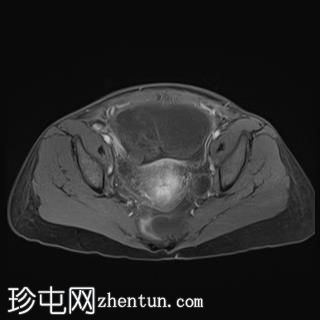

轴位

T1加权像

T1加权像平扫显示T1高信号,与CT上的高密度部分相对应,增强后无强化,符合血液成分表现。

T2加权像显示复杂囊性肿块,内含出血性物质,右侧卵巢未显影。注意卵巢蒂扭转。

影像表现提示附件扭转。患者被送入手术室行剖腹探查术。